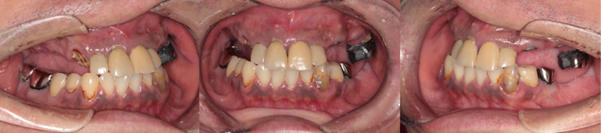

インプラント症例1

Before

インプラント症例1 治療前

治療内容

喫煙習慣があったので、禁煙していただきました。患者様は大変熱心に習慣の改善に努められました。

上顎は全ての残存歯でむし歯が大きく、保存不可能でしたので抜歯して無歯顎状態にし、臼歯部は顎堤の委縮が著しかったためサイナスリフトを両側に行い、10カ月待機後、8本のインプラントを埋入し、7カ月待機後チタンとジルコニア製の上部構造を装着しました。

左下4、5歯は、上顎手術の待機期間を利用して治療を行いました。むし歯のため保存不可でしたので抜歯と同時に骨造成を行い、骨の治癒を待った後、左下4、6部に2本インプラントを埋入し、ブリッジタイプの上部構造を装着しました。

右下の臼歯もむし歯の為、本来は抜歯しなければならないのですが、患者様のご都合により、保存しています。